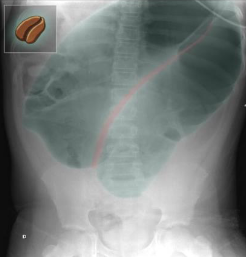

A. Imaging examination

X-ray abdomen (AP view)

What is the name of Sign & what does it usually mean? Markedly dilated bowel . The configuration, including the double wall thickness of the two apposed bowel loops, resembles a bean “coffee bean sign”.

Diagnosis Sigmoid volvulus